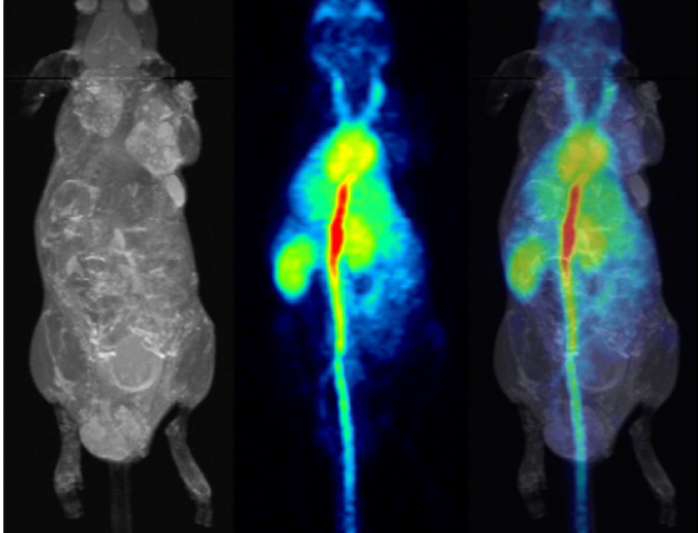

pmod’s tools provide comprehensive workflows for post-processing and quantification of imaging data for fundamental oncology research, development of radiotracers and theranostics, and in clinical research studies. Imaging scientists can trust pmod to reproducibly read their data, interpret the meta-data/units and help users calculate statistics such as SUV for their studies and publications.

For treatment evaluation and theranostic development

• Multimodality segmentation tools – comprehensive semi-automated and manual tools for precision and reproducibility

• Flexible switching between 3D and 4D datasets – direct output of time activity curves